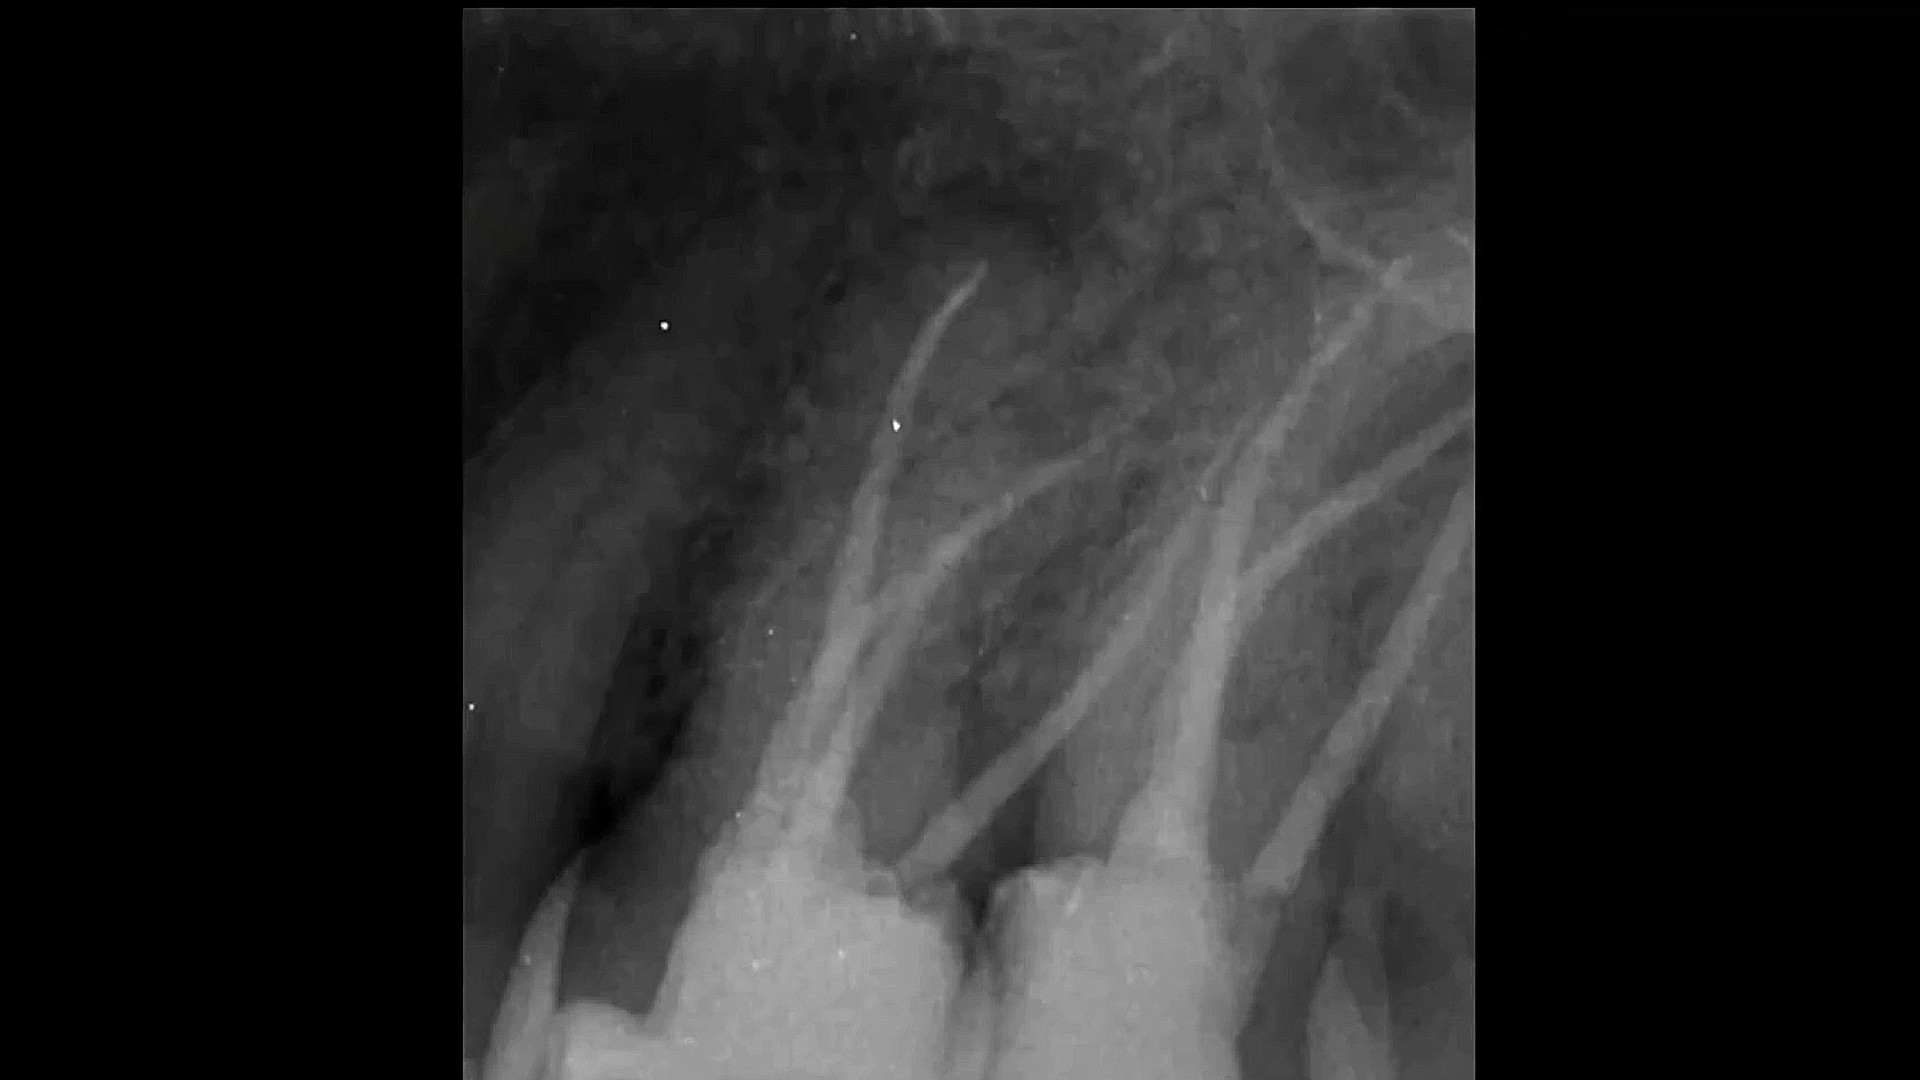

HOW TO MANAGE LARGE PERIAPICAL LESION WITH NON-SURGICAL ENDODONTIC TREATMENT